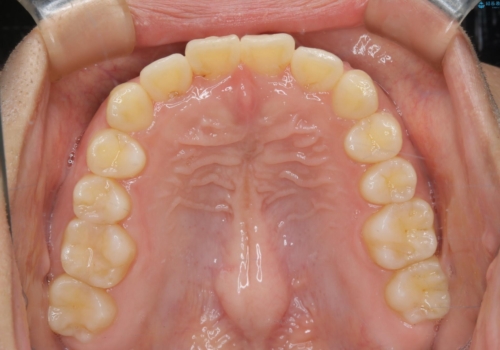

- 前歯が捻転していることを主訴に来院された方です。元々は部分矯正をご希望されていましたが、噛み合わせ等総合的に治療していくためインビザラインにて全顎的に治療を行うこととしました。

元々は上の前歯部の捻転のみの治療をご希望されていましたが、下の前歯もがたつきがあることや噛み合わせがかなり深いことを説明しました。後戻りのリスクを抑えるために全顎的な治療をご提案しました。

捻転していた上顎前歯部の仕上がりにこだわり、何度か修正を行ったため、満足のいく仕上がりになったと大変喜んでいただけました。